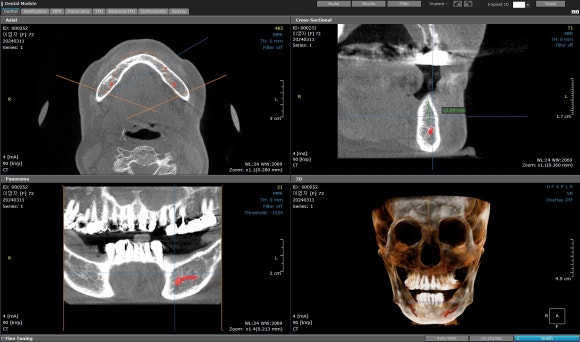

CT를 분석해보면

정말 “뼈가 없다”라고 표현할 만큼

어려운 상황이었습니다.

하지만

모든 뼈가 없는 건 아닙니다.

얇아도, 작은 영역이라도

단단한 기저골은 반드시 존재합니다.

이번 케이스에서도

그 기저골을 하나하나 찾아내

픽스쳐가 최대한

‘튼튼한 곳’을 잡을 수 있도록

각도를 미세하게 조정하며 식립했습니다.